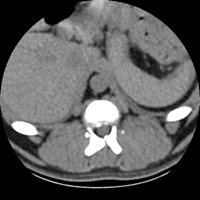

La tomodensitométrie axiale assistée par ordinateur, autrement appelée scanner à rayons X ou plus simplement scanner, est une technique d'imagerie médicale permettant de réaliser des images radiographiques en coupes anatomiques perpendiculaires à l'axe du corps du patient.

À partir des coupes natives axiales du patient, des logiciels de reconstruction permettent de faire des reformatages dans tous les autres plans (sagital, coronal ou oblique). Enfin, des reconstructions tridimensionnelles peuvent aussi être réalisées avec un rendu volumique, surfacique ou endoscopique.

Par rapport à la radiographie conventionnelle, le scanner permet donc une dessuperposition des structures anatomiques, et ce, avec une meilleure résolution en contraste.